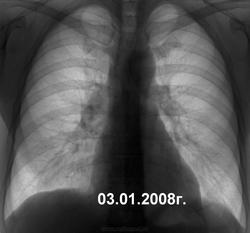

Я так понимаю , что не понравились малоинтенсивные тени в латеральных отделах слева ? Кнаружи от среднеключичной линии ?  В ГТД его родимого !

Вижу именно то, что отметил Фил. Может там ТБС и не будет, и его еще куда отправят, но будет участие. По крайней мере не скажут, что ничего не видел, не внимательно смотрел. Потом это будет всем видно.

что Игорь Иванович поступил тактически правильно. Больше всего боюсь в таких случаях госпитализации пациентов в туберкулезный стационар. Подобных больных следует быстро обследовать амбулаторно. Возможно, имеется нетуберкулезная патология (саркоидоз?). Не по душе мне и эта тень (см. рисунок). Надеюсь получим сведения об окончательном диагнозе. С уважением Nikolas